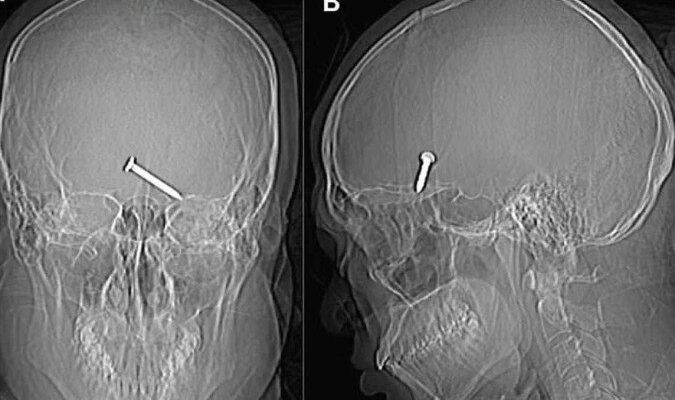

Um raio-x do crânio mostrou que o prego de três centímetros havia se alojado no cérebro do homem. Uma parte do crânio foi quebrada pelo impacto. No hospital, apesar da gravidade do ferimento, a vítima apresentava bons sinais vitais.